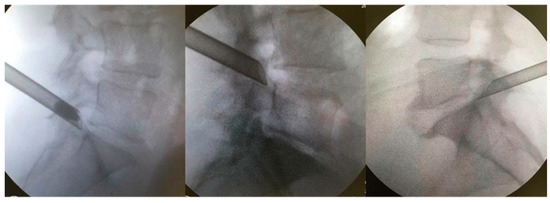

Figure 2.

Extraforaminal position of the working cannula before foraminoplasty is supported by the caudal vertebra’s SAP.

The patients were kept under conscious sedation in a prone position on a radiolucent table for the surgical procedure, with their hips and knees partially flexed. The marking of the entry point on the skin was confirmed with the image intensifier’s aid, laterally, approximately 11–12 cm from the midline. Local anesthesia was performed with 1% lidocaine without a vasoconstrictor in the following structures: skin; subcutaneous tissue; paravertebral musculature; and peri-facet region. Initially, we introduced the work sleeve, and under direct supervision, we performed the foraminoplasty with a drill. We believe that this makes the procedure safer and allows it to be performed in cases in which the Kambin’s triangle is very small. A 18-gauge needle was then introduced to the lateral portion of the superior articular process (SAP) of the caudal vertebra. The final target point was confirmed using fluoroscopy in the anteroposterior and lateral views. From there, a guidewire, dilator, and beveled working cannula were inserted at 70°; subsequently, the 30° inclination endoscope and 4.2 mm working channel, accompanied by continuous saline irrigation, were introduced [17]. The opening of the working cannula was supported by the SAP of the caudal vertebra (Figure 2). Bipolar electrocautery was used to perform hemostasis; it was connected to the Surgimax device. A foraminoplasty cutting drill was used to remove the bone from part of the SAP of the caudal vertebra. The foraminal ligaments and lateral portion of the yellow ligament were removed using a rotating Kerrison or endoscopic forceps. After foraminoplasty, the cannula advanced towards the disk, which had its herniated fragment easily identified and removed with the aid of endoscopic disk forceps (outside-in technique). In cases of bone stenosis only, the disk was not addressed (outside-out approach). Foraminoplasty and diskectomy were performed after direct visualization of the decompressed root in the foramen (emergent root) or lateral recess (transversing root). After the procedure, all patients were allocated to a continuous physical rehabilitation program and monitored for 24 months.